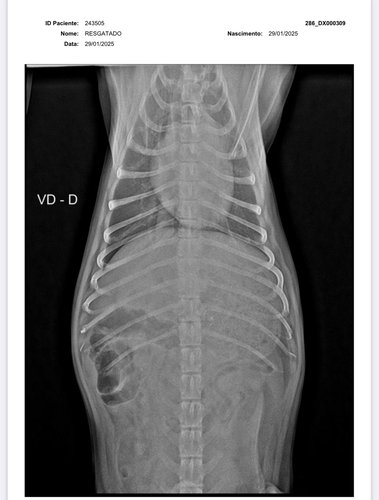

olá, eu sou a Samira, ajudo em uma ong de animais em Vilhena-RO e também resgato animais por conta própria. Encontrei esse pequeno cachorrinho abandonado a dias na chuva, sentindo tanta dor a ponto de não aceitar um sachê de comida. Levei ao veterinário e após buscar vários orçamentos, cheguei ao valor da vakinha, juntamente com a clínica Veterinária SOS animal, para a cirurgia do pequeno guerreiro. Não possuo condições de arcar com 100% da cirurgia, portanto, peço encarecidamente a ajuda de vocês para me ajudar e salvar a vida desse pequeno guerreiro. * Deixo abaixo o orçamento e os exames !